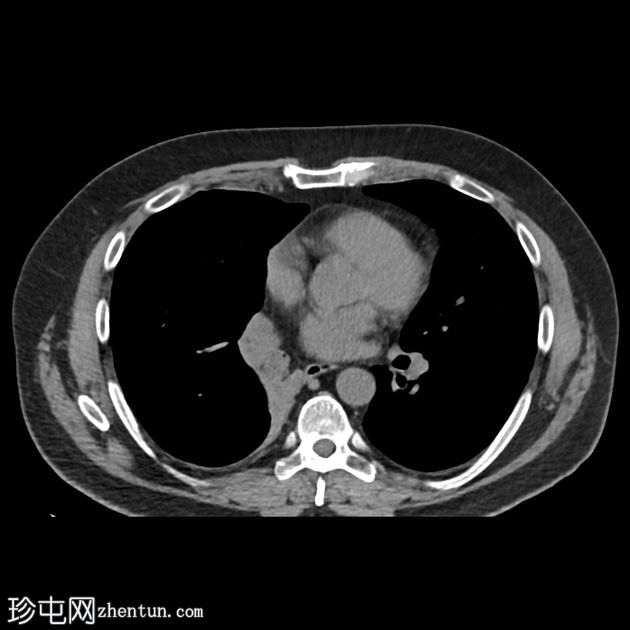

初始CT检查

CT

在一次时机不佳的动脉期CT扫描中,我们发现右下支气管内有一个低强化肿块。

左肾内偶然发现一个较大的、中心坏死的肿块。

右侧肾上腺可见几个小的低密度结节。

另需注意环状伪影(CT机随后不久更换)。

支气管镜检查发现右侧支气管树内有一个坏死性肿块,组织学诊断为肾细胞癌转移。

患者接受了左侧肾切除术,并开始接受联合免疫治疗。